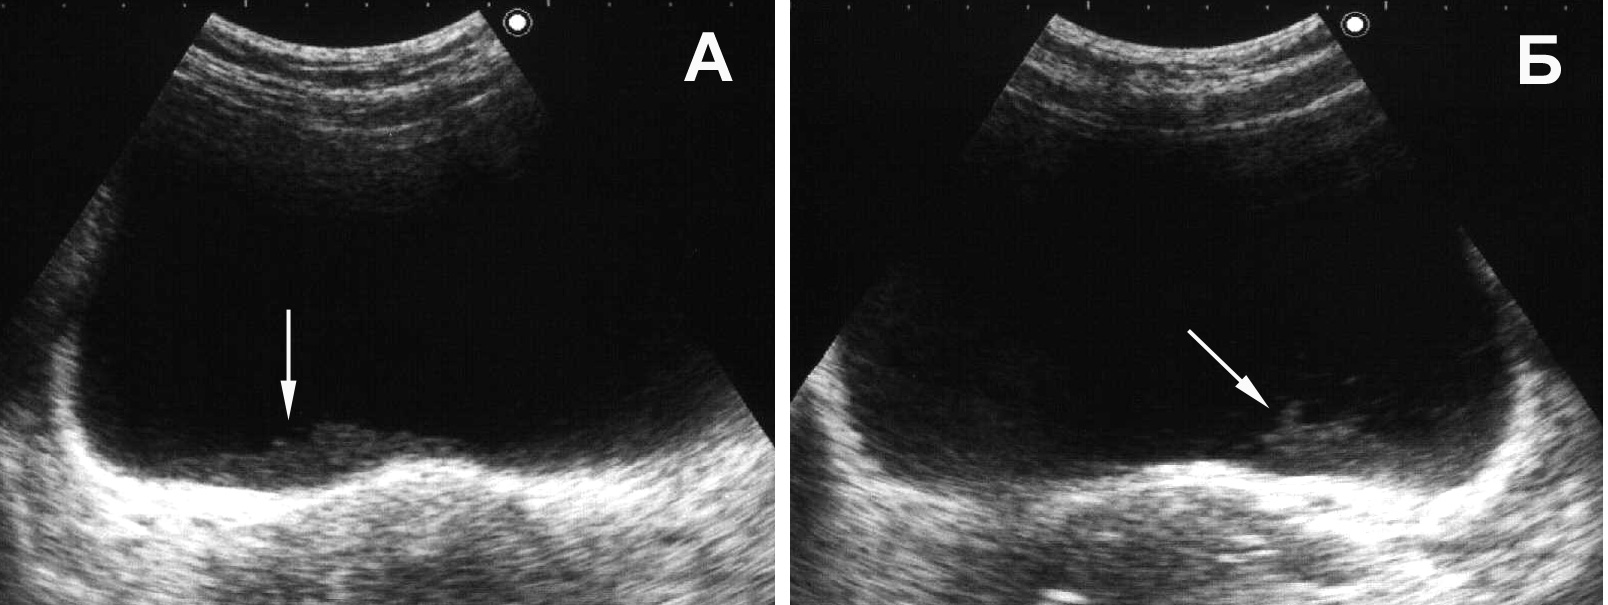

Рис. 17. Мочевой пузырь при цистите, пиурии. Вязкий гной образует причудливые фигуры на дне пузыря, при изменении положения тела он медленно перемещается, почти не меняя формы. (Поперечное сканирование, А − в положении пациента на спине, Б − на левом боку. Конвексный датчик 5 МГц, “Logiq-500”).